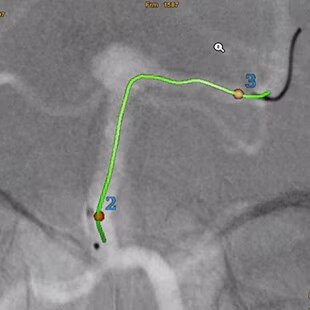

Plan

Automatically extract the bone and vessel anatomies. Edit vessel centerlines and bridge them through occlusions.

Guide

Select from the sub-volumes of vessels, centerlines, calcifications and landmarks to overlay on live fluoroscopy for 3D fusion guidance, with digital zoom, to guide recanalization.